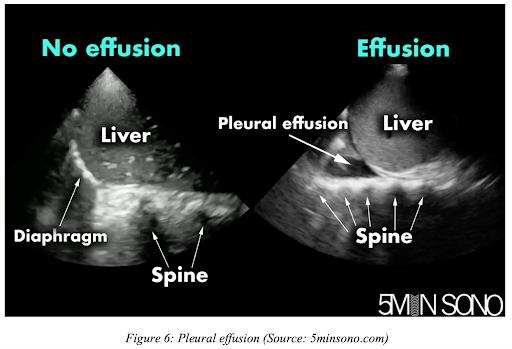

Epanchement pleural